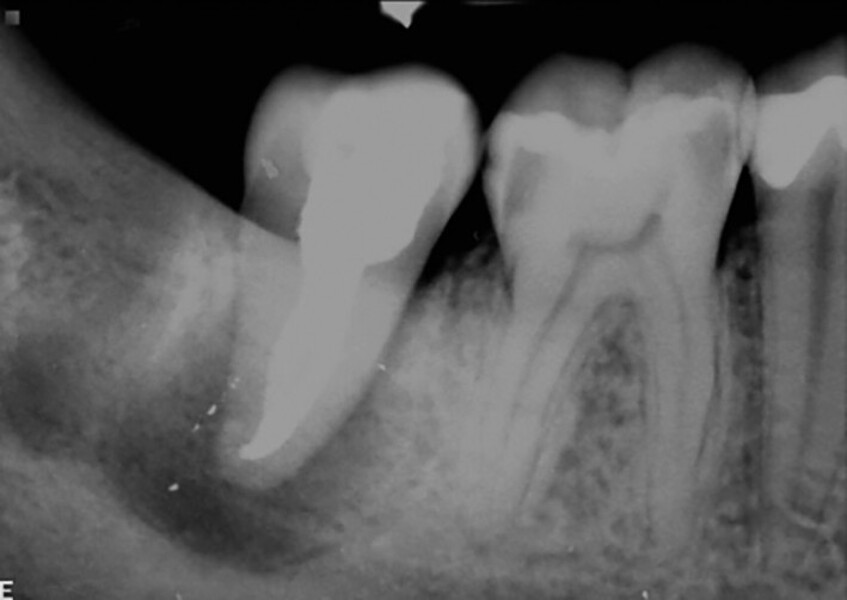

Fig. 19a: Radiographs: Pre-op periapical.